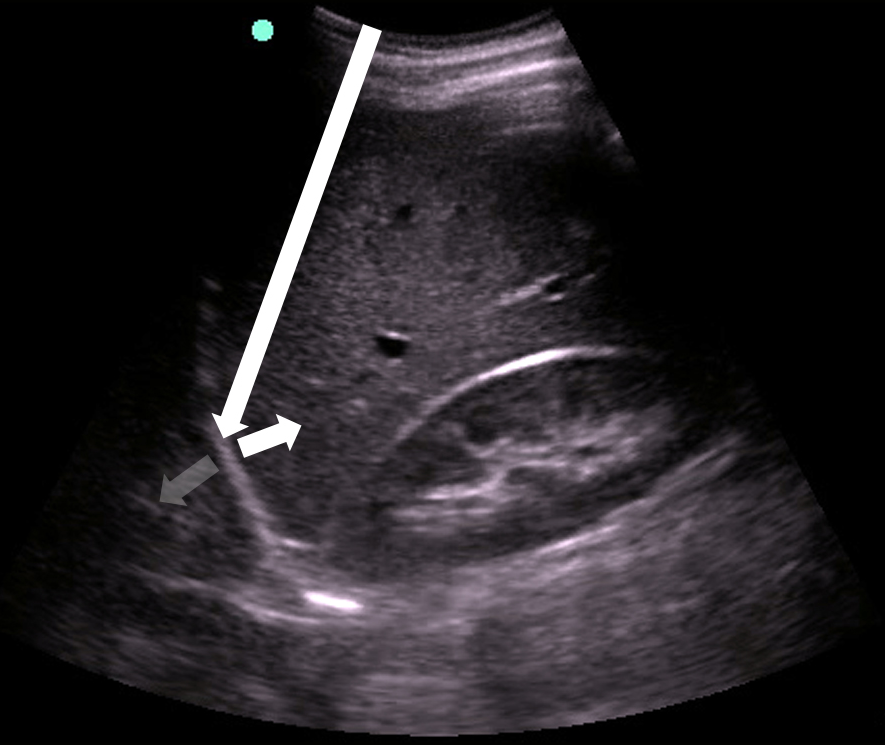

Pleural Effusion

- Anechoic space between parietal and visceral pleura78

- Normal air-filled lung is replaced by liquid-dense effusion, which now allows propagation of sound waves.

- Figure 18. Pleural effusion with spine sign

- Quad sign delineates four boundaries: superior and inferior rib shadows, superficial parietal pleura, and the deeper visceral pleura.

- Figure 19. Pleural effusion with quad sign